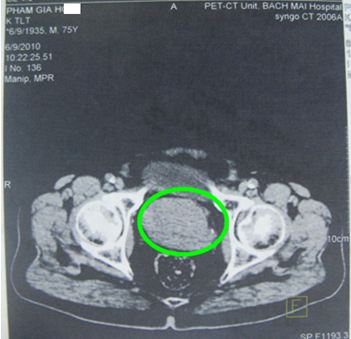

Kết quả siêu âm (đầu dò trực tràng): Tuyến tiền liệt to 86g, không đồng nhất có nhiều nốt vôi hoá, bờ không rõ, chèn ép niệu đạo tuyến tiền liệt, xâm lấn túi tinh trái. Như vậy chúng tôi đánh giá u nguyên phát là T3 (u xâm lấn qua vỏ bao tuyến) theo phân loại TNM của tổ chức Y tế thế giới.

Hình ảnh siêu âm (đầu dò trực tràng): tuyến tiền liệt (trong vòng tròn màu vàng) có âm không đồng nhất, nhiều nốt vôi hóa.